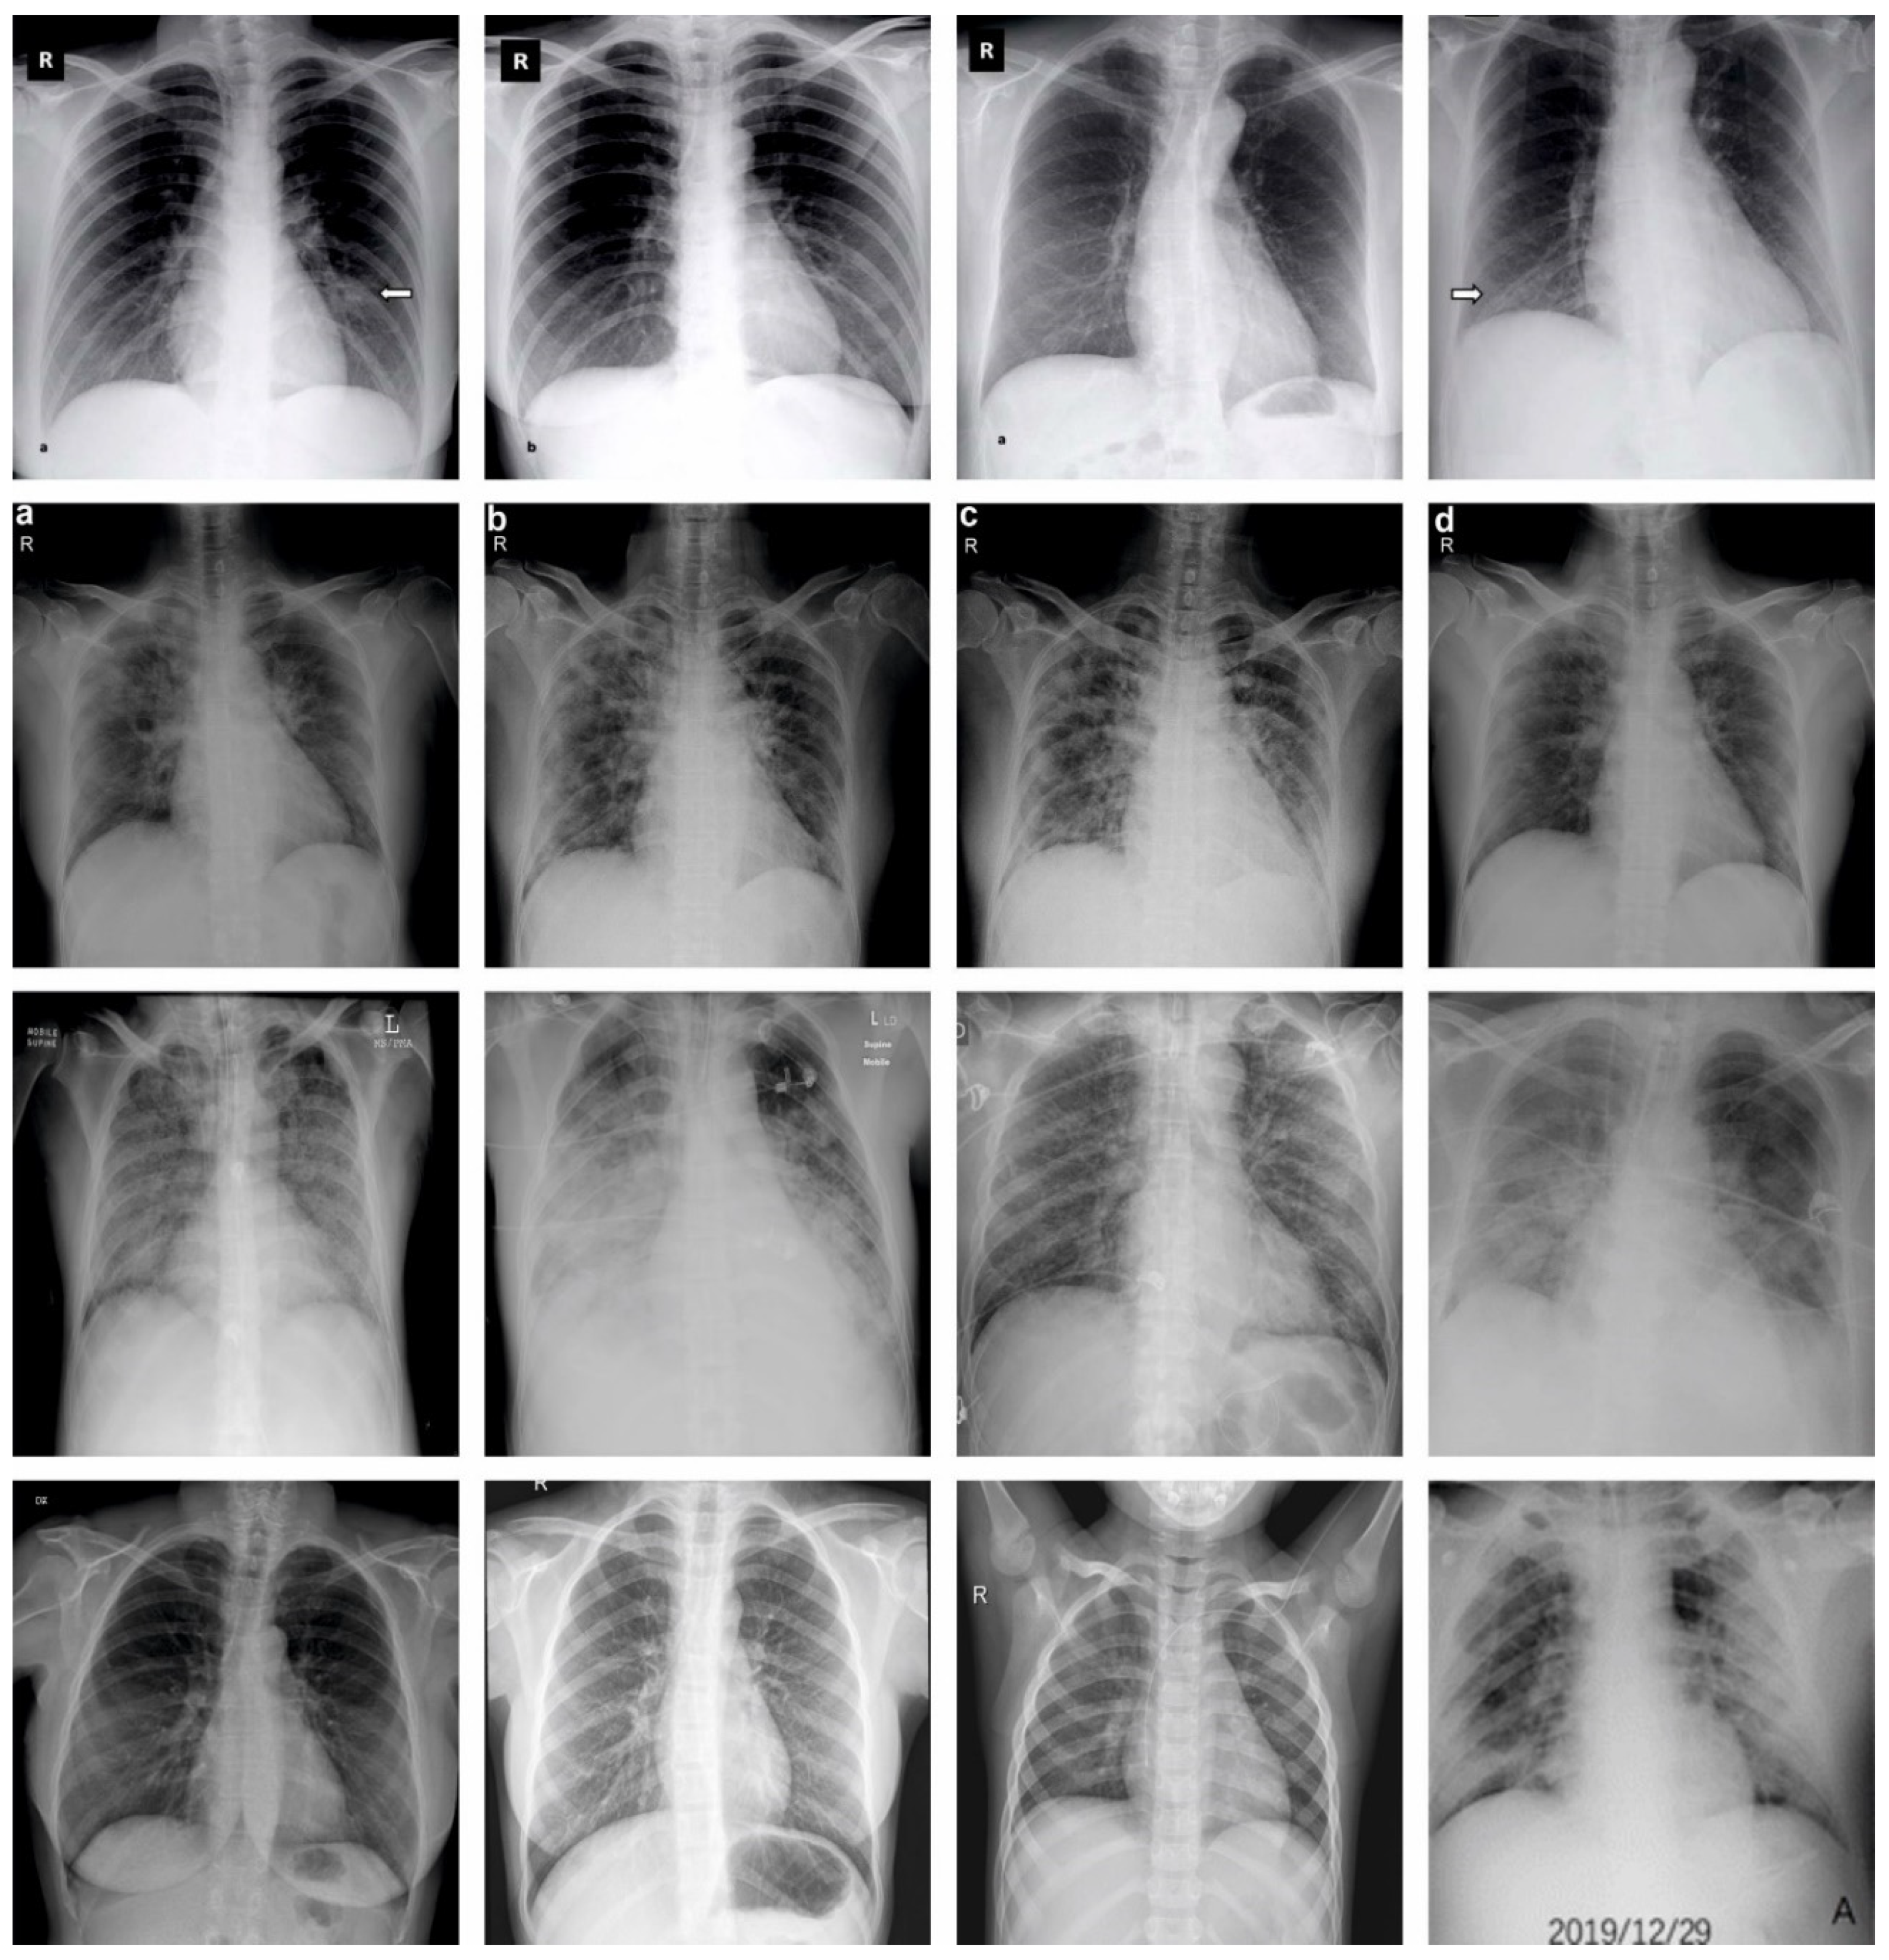

In this section, the experimental validation of the SCODL-DDC technique is tested on the CXR image dataset [33], comprising 305 samples with different classes as defined in Table 1. Figure 3 represents the sample images.

Figure 3. Sample images (A: airways; B: breathing; C: circulation; D: disability; R: Rotation; Arrow Mark: Opacities).